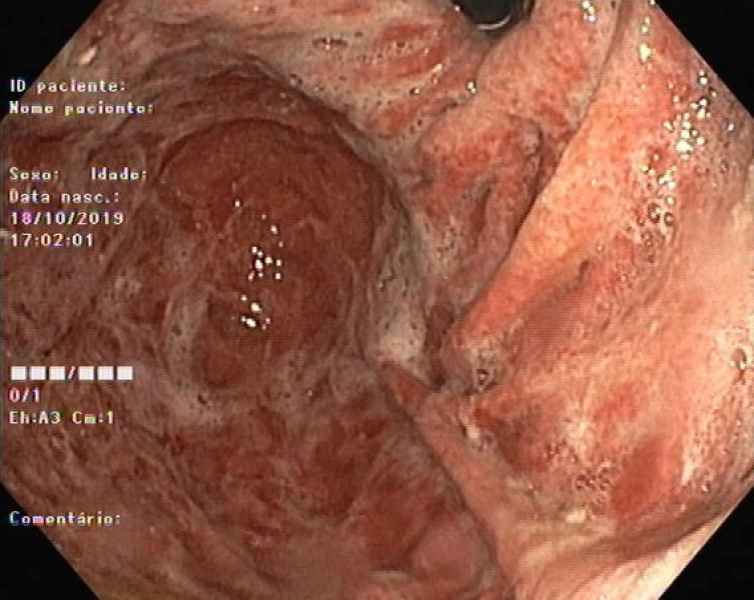

From IPMN to IPMN-derived invasive adenocarcinoma